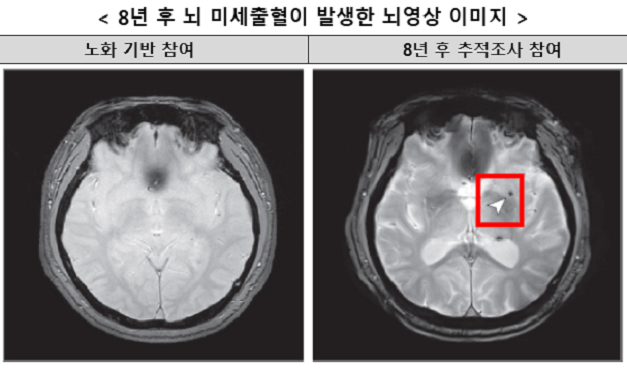

질병관리청 국립보건연구원은 28일 한국인유전체역학조사사업(KoGES)의 안산 코호트를 통해 8년간 중장년층 1441명을 추적 조사한 결과, 중등도 이상의 수면무호흡증이 뇌 미세출혈 위험을 약 2배 증가시킨다는 연구 결과를 발표했다.

이번 연구는 고려대학교 김난희 교수 연구팀이 진행했으며, 수면무호흡증의 중증도가 뇌 미세출혈 발생에 미치는 영향을 분석했다. 연구에 따르면 중등도 이상의 폐쇄성 수면무호흡증을 가진 사람은 수면무호흡증이 없는 사람에 비해 뇌 미세출혈 발생 위험이 약 2배 증가했다. 반면 경증 수면무호흡증에서는 위험 증가가 관찰되지 않았다.

수면무호흡증은 잠자는 동안 호흡이 멈추거나 약해지는 현상으로, 호흡장애가 시간당 얼마나 반복되는지에 따라 경증, 중등도, 중증으로 분류된다. 뇌 미세출혈은 뇌 속의 작은 혈관이 손상되어 출혈이 발생하는 것으로, 뇌졸중 등 심각한 뇌혈관 질환의 주요 위험 요인으로 알려져 있다.

연구 결과는 뇌혈관질환 발생 위험과 관련된 특정 유전자 보유 여부와는 상관없이 수면무호흡증 자체가 뇌 미세출혈 발생 위험을 높이는 독립적인 위험 요인임을 확인했다. 연구진은 “수면 중 심한 코골이나 숨이 잠시 멈추는 듯한 현상, 낮 동안 과도한 졸림이 빈번하게 나타난다면 전문의를 통해 정확한 진단을 받고 적극적으로 치료할 필요가 있다”고 강조했다.